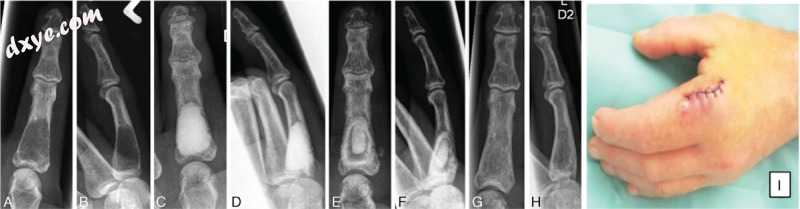

在软骨瘤肿瘤刮除术后,12名患者(2名女性,10名男性)平均年龄为42.42±17.2岁,用Cerament治疗。 发生了根据Clavien-Dindo分类[9]的II级并发症。 7例患者(53.8%)出现红肿,持续至术后10天(图3).3)。 在这些病例中,口服抗生素治疗(第二代头孢菌素)在术后第一天开始,持续7天。 在这些患者中的一个中,在强化理疗期间手术后2周出现骨水泥中区的骨折。 这种骨折在保守治疗后愈合良好,但该患者需要夹板6周。 1例患者出现慢性区域性疼痛综合征(CRPS),经强化保守治疗成功治疗,1年内无任何残留症状愈合。

3.jpg

图3

术前2周,术后直接术后刮除和使用Cerament(C,D)术后直接术后(A,B)近端指骨35度患者的左侧第二位X射线照片 (E,F),手术后8周(G,H)。 术后出现红肿,术后第3天,由于乳状引流(I)。